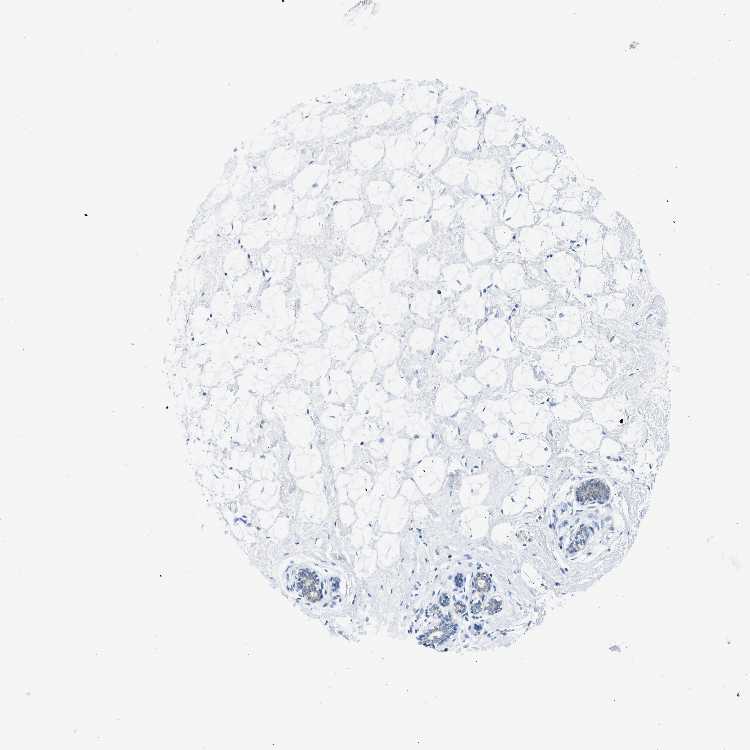

BREAST - Antibody stainingi

Antibody staining in the annotated cell types in the current human tissue is reported as not detected, low, medium, or high, based on conventional immunohistochemistry profiling in selected tissues. This score is based on the combination of the staining intensity and fraction of stained cells.

Each image is clickable and will lead to virtual microscopy that enables deeper exploration of all samples and also displays staining intensity scores, fraction scores and subcellular localization as well as patient and tissue information for each sample.

Antibody HPA016802

Adipocytes Not detected

Glandular cells Not detected

Myoepithelial cells Not detected